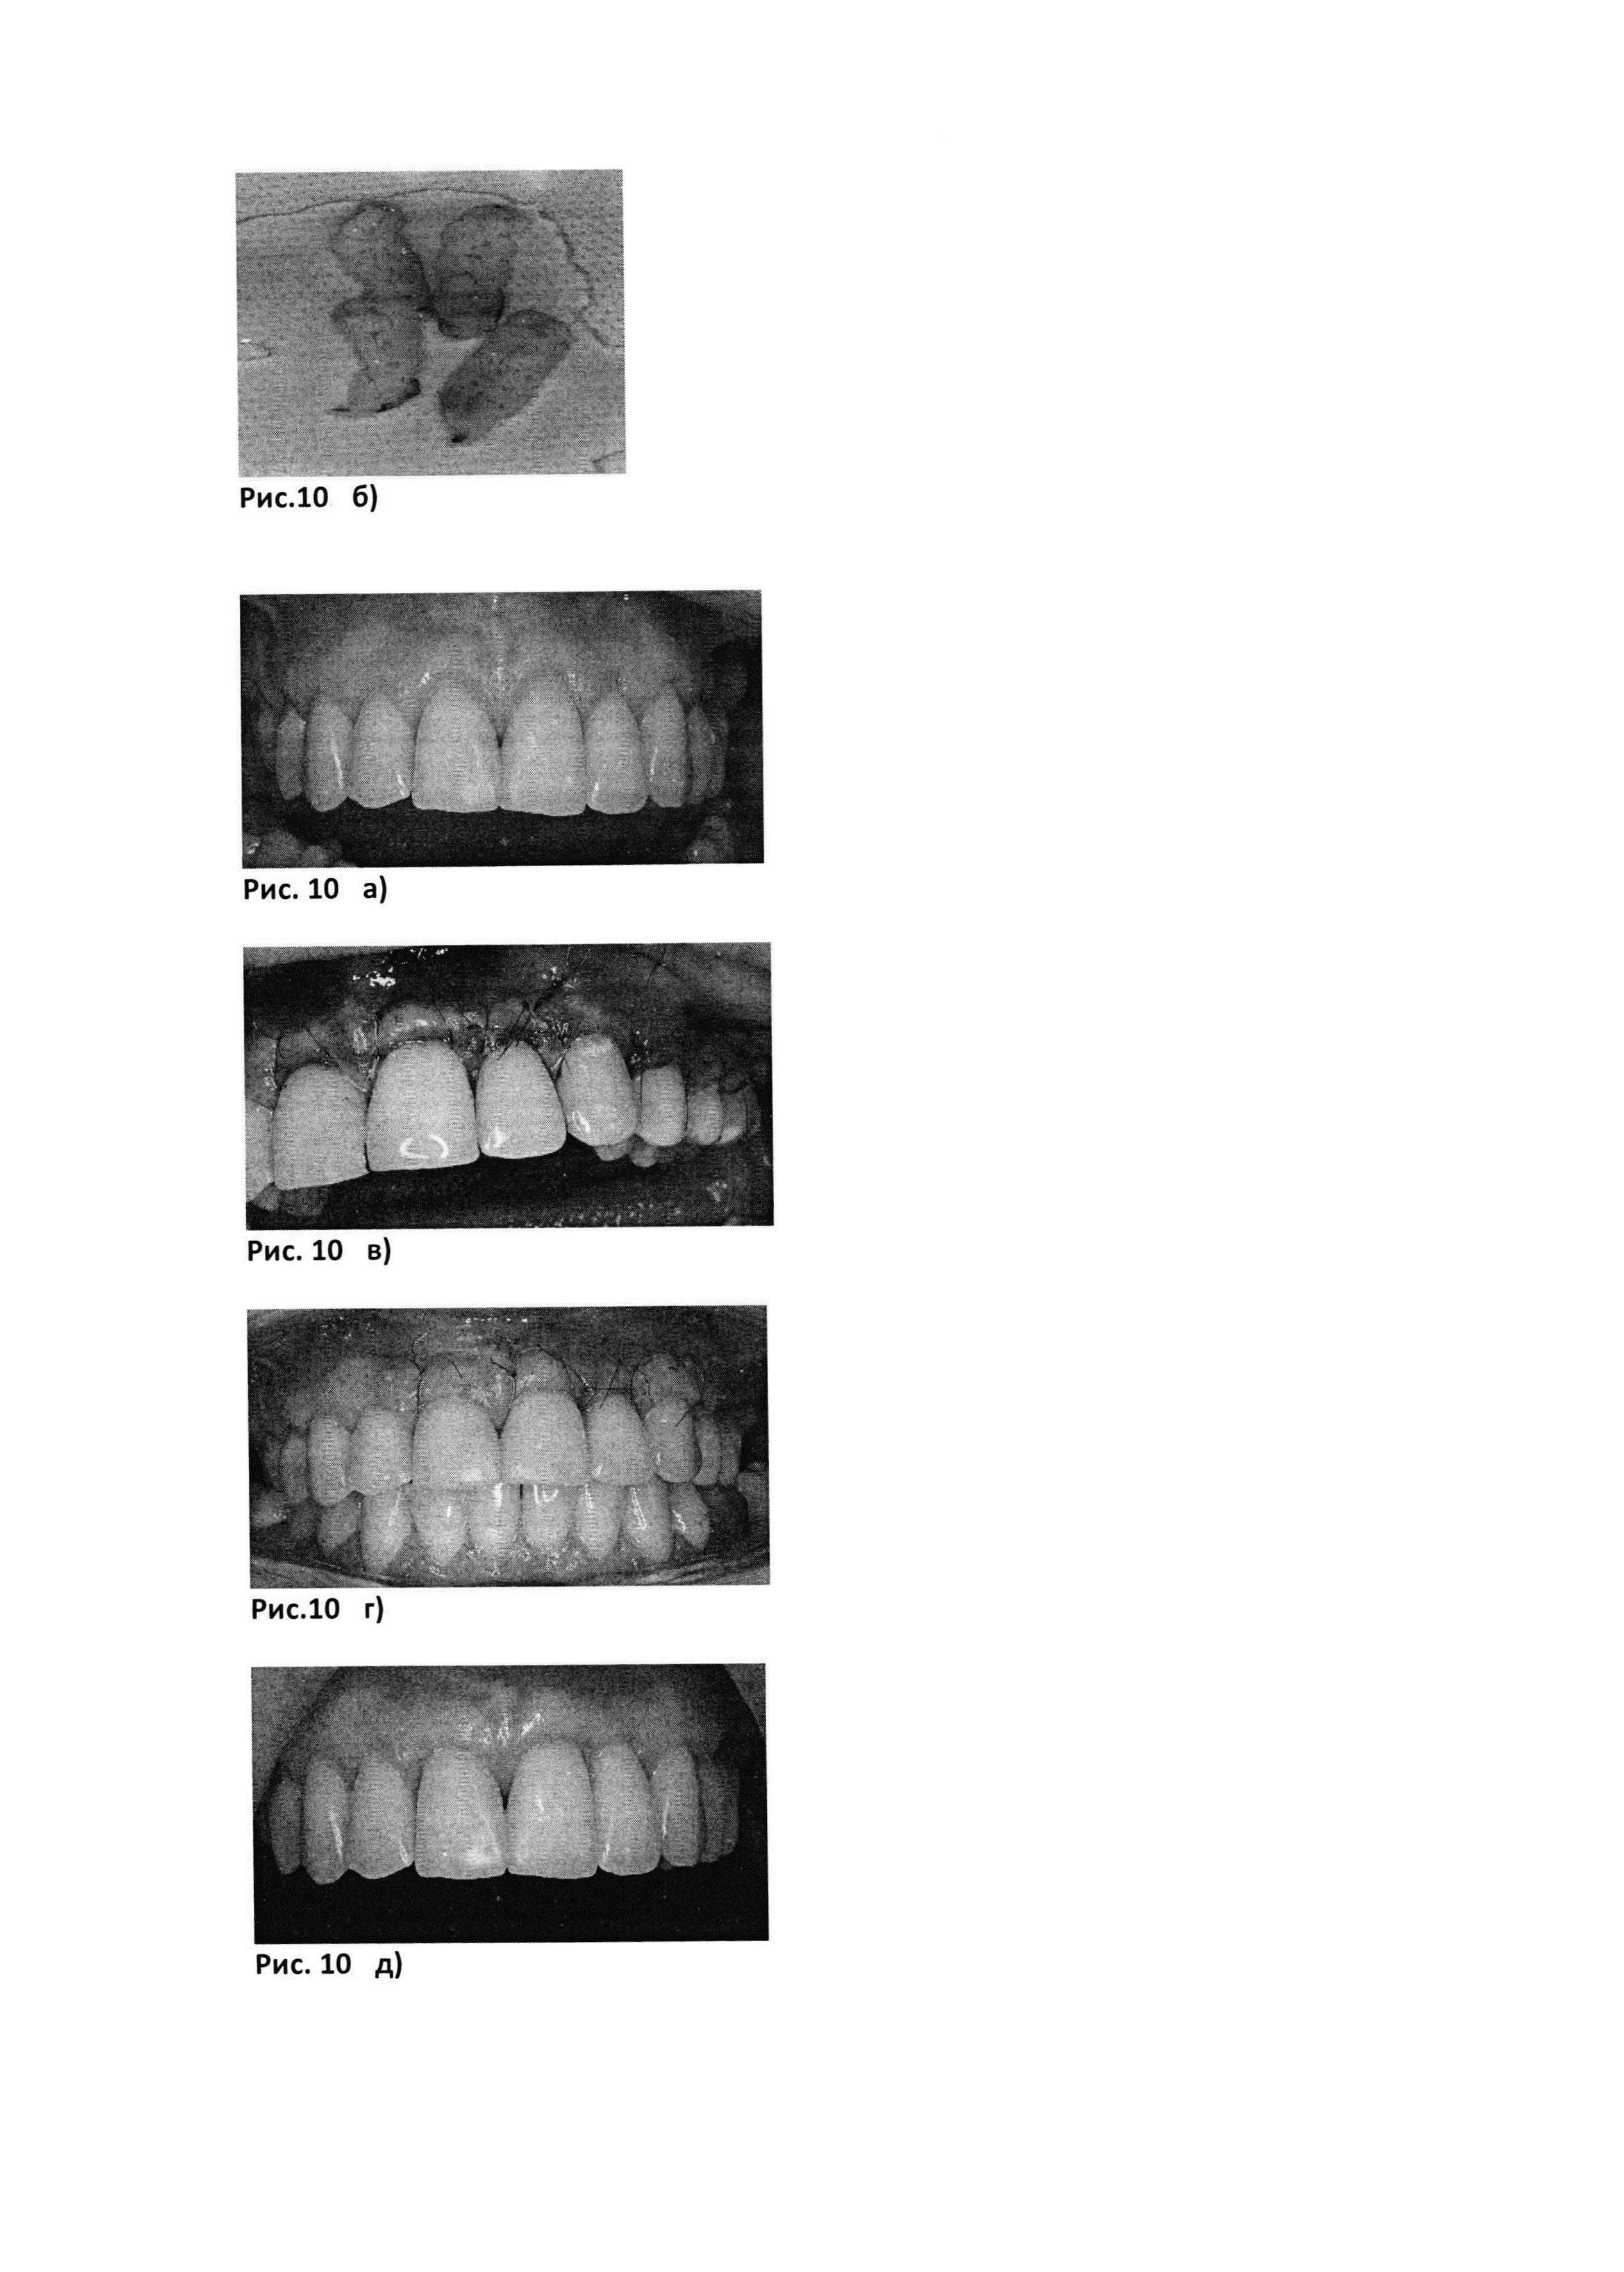

Рис. 10. б). Биотрансплантаты, представляющие собой PRF-мембраны (полученные с помощью центрифуги Scilogex, USA (РУ №РЗН 2015/3442) с интегрированными в них аутоФС пациента.

Рис. 10. а) до лечения

Рис. 10. в) сразу после операции

Рис. 10. г) через 12 дней после операции

Рис. 10. д) через месяц после операции

Рис. 10. е) через 3 месяца после операции

Рис. 10. ж) через 6 месяцев после операции